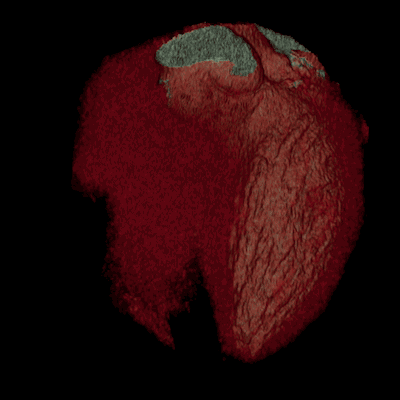

05真实的心脏跳动示意图